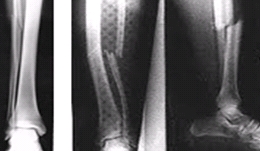

이러한 골다공증이 생기면 뼈가 아프고,

가벼운 충격에도 쉽게 뼈가 부러질 수 있고,

그로 인해 통증이 발생할 수 있습니다.